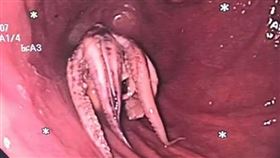

男食道挖出「整隻章魚」 觸手卡死畫面曝

新加坡一名55歲男子因吞嚥困難,感到不適而前往就醫,...

男吞嚥困難!醫一查驚見「活章魚」卡食道

許多人喜歡吃生食,不過也得格外小心。新加坡一名男子食...